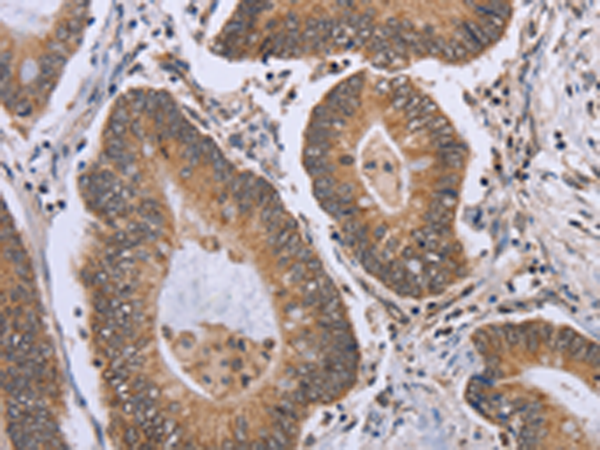

分类: 科研抗体货号: P08272别名: EIF-4B; PRO1843应用: IHC反应种属: Human, Mouse